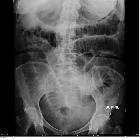

medical management of emphysematous gastritis with concomitant portal venous air: a case report. Scout film showing air along the greater curvature of the stomach.